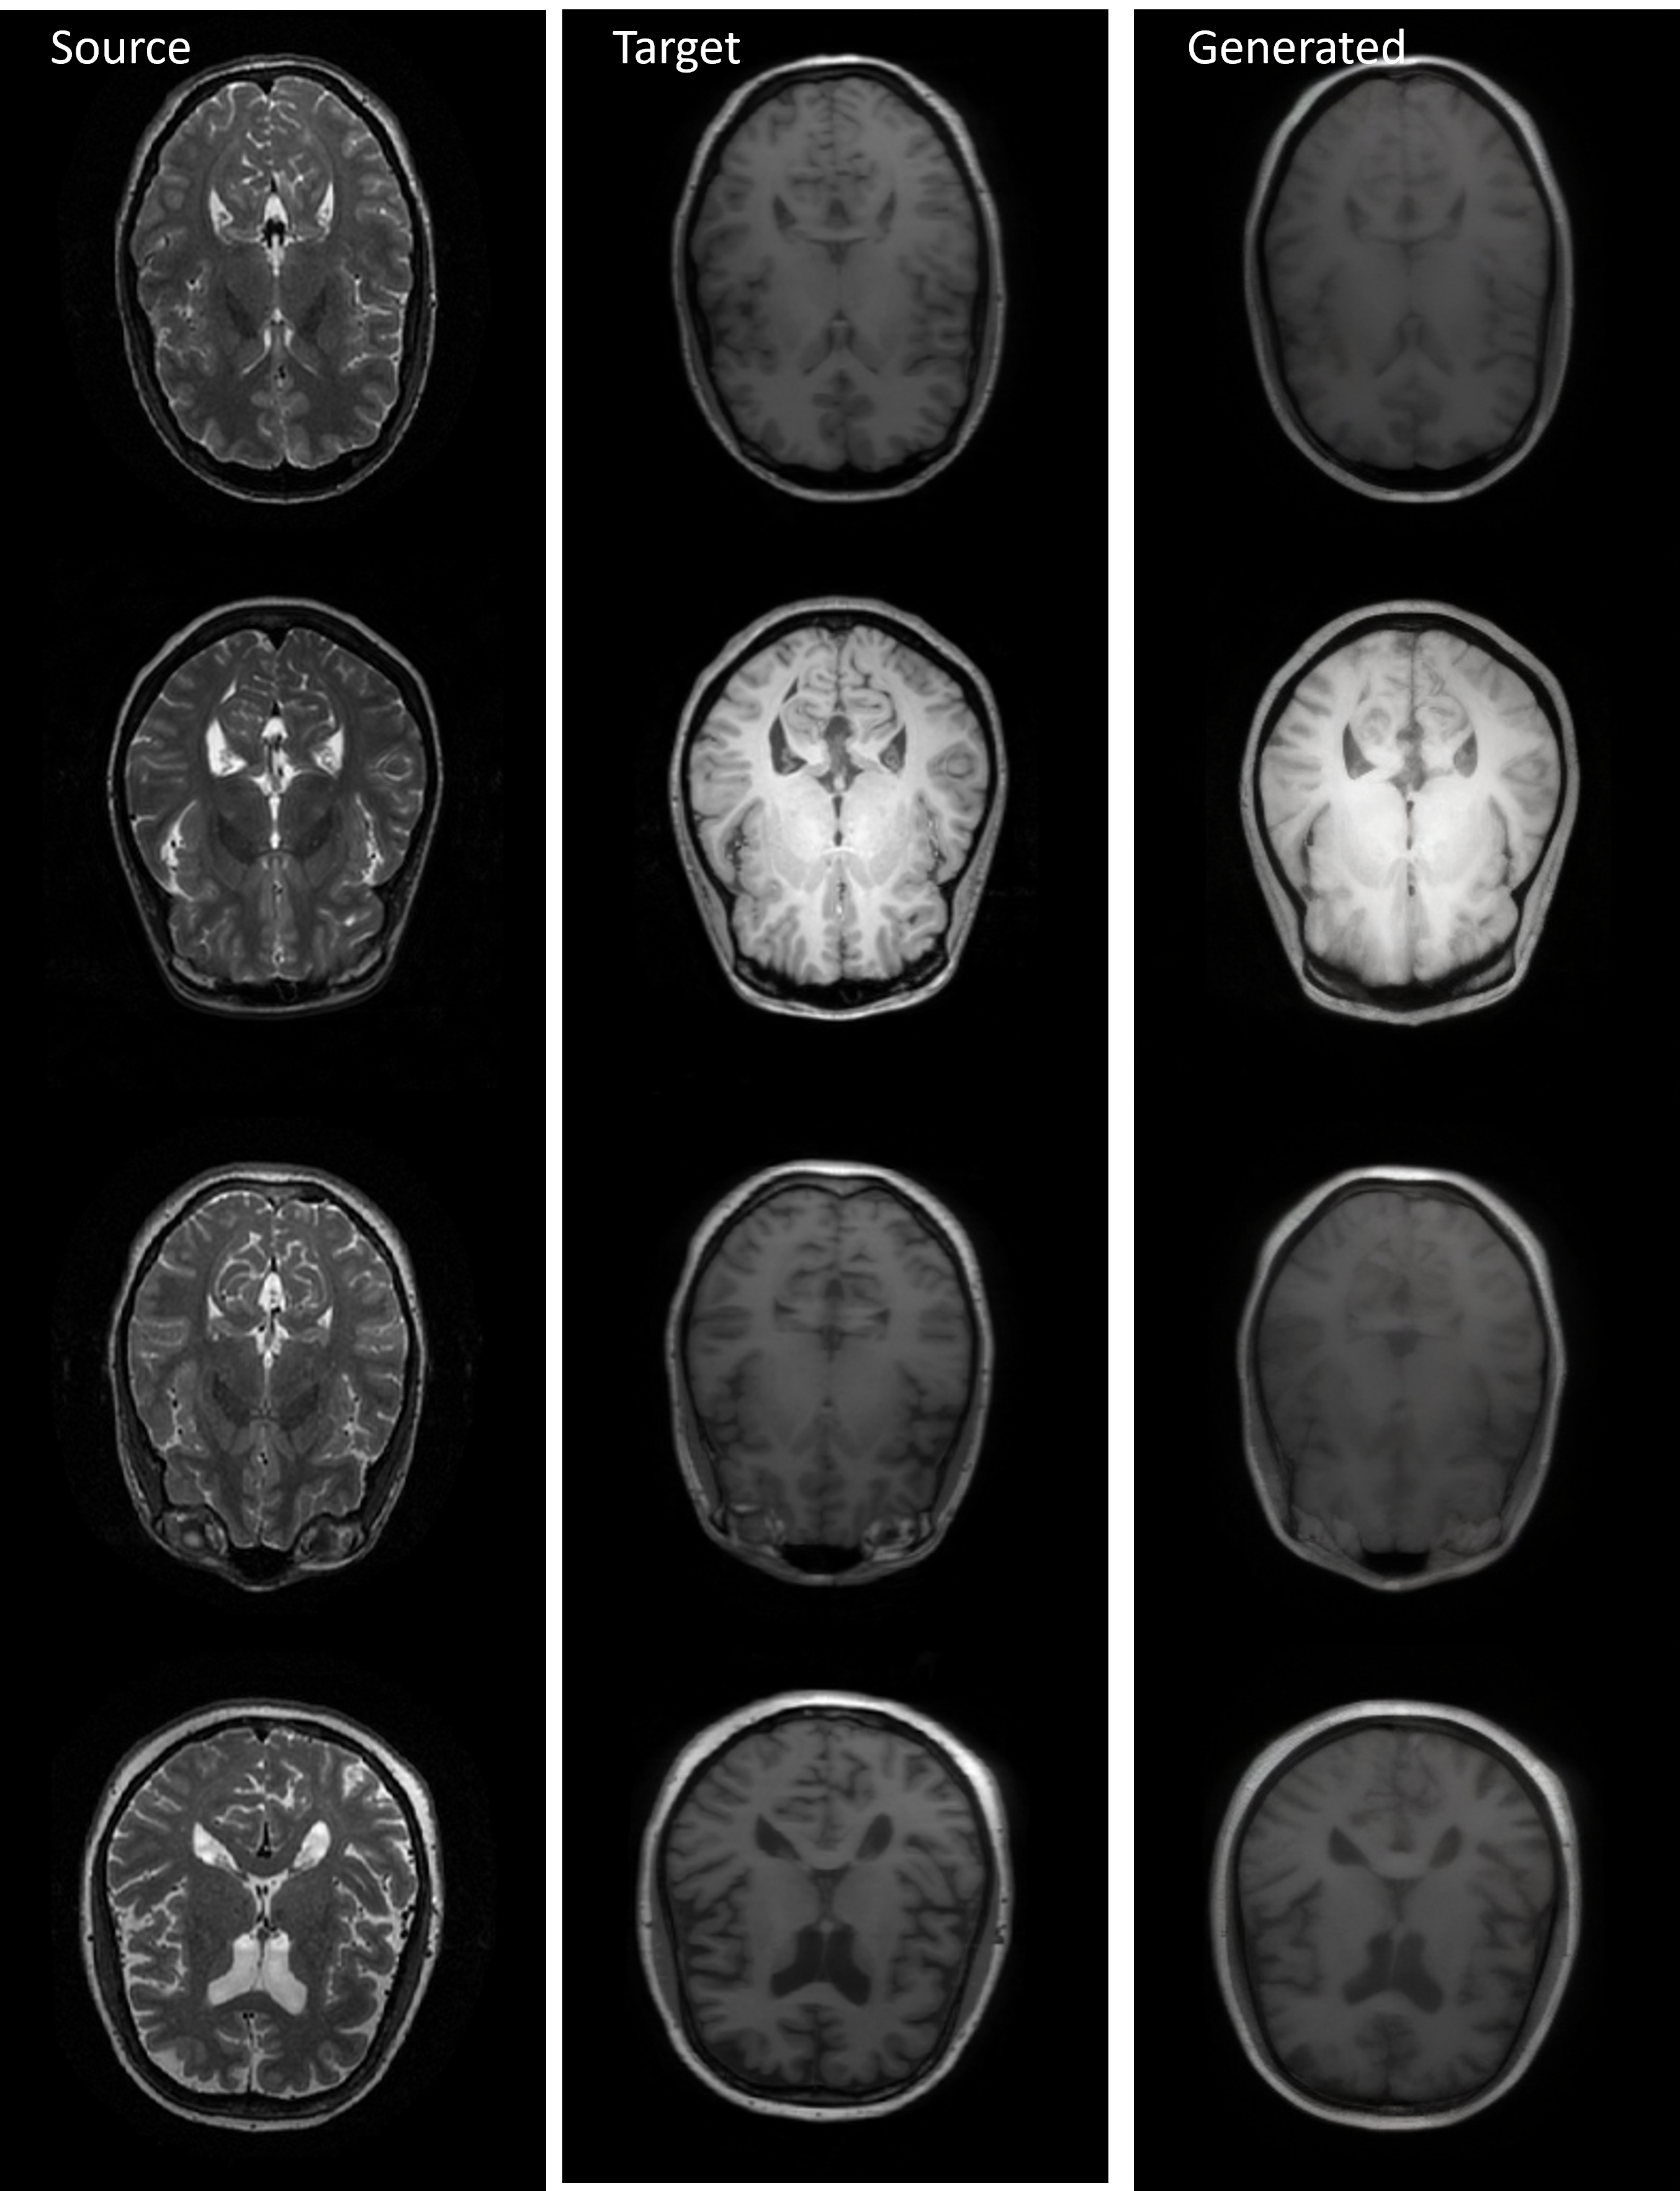

Refer to caption

Figure 2: Visual comparison across three cross-modal tasks: IXI medical conversion, Sentinel SAR-to-optical, and PSCDE semantic mask. (See more in Appendix 6.15).

IXI & Sentinel Datasets: Fig. 2 shows that on IXI, CDTSDE reconstructs anatomically coherent images with crisp cortical and ventricular boundaries. It improves over DOSSR, which slightly smooths details, and clearly surpasses Pix2Pix and the bridge-based methods (DBIM, ABridge, BBDM), which exhibit blur, noise, or partial structural collapse. On Sentinel (SAR\rightarrowOPT), CDTSDE produces semantically aligned, natural optical images with stable geometry, while DOSSR loses fine detail, Pix2Pix exaggerates colors and textures, and the bridge-based methods leave fragmented or inconsistent patterns even when DBIM locally improves contrast.

Medical Image Translation (IXI: T1\leftrightarrowT2) Across both directions on IXI, CDTSDE consistently delivers the strongest fidelity. For T1\rightarrowT2 it attains the highest SSIM (0.762±0.042)(0.762\pm 0.042) and PSNR (23.32±1.25dB)(23.32\pm 1.25\,\text{dB}) with the lowest MSE (0.0049±0.0016)(0.0049\pm 0.0016); for T2\rightarrowT1 it further improves to SSIM (0.825±0.038)(0.825\pm 0.038), PSNR (24.33±1.86dB)(24.33\pm 1.86\,\text{dB}), MSE (0.0040±0.0018)(0.0040\pm 0.0018), and MAE (0.0324±0.0076)(0.0324\pm 0.0076). Among diffusion bridge-based methods, DBIM improves over other bridge-based ABridge and BBDM on PSNR/MSE/MAE (e.g., for T2\rightarrowT1 it reaches SSIM (0.33±0.04)(0.33\pm 0.04), PSNR (21.65±1.45dB)(21.65\pm 1.45\,\text{dB}), MSE (0.010±0.004)(0.010\pm 0.004), MAE (0.060±0.015)(0.060\pm 0.015)) yet still lags behind Pix2Pix, DOSSR, and CDTSDE in structural fidelity. DOSSR is a close second in SSIM/PSNR/MSE and attains the lowest MAE on T1\rightarrowT2 (0.0321±0.0060)(0.0321\pm 0.0060). Pix2Pix is weaker, and ABridge and BBDM show marked degradation and structural artifacts consistent with their low SSIM/PSNR.